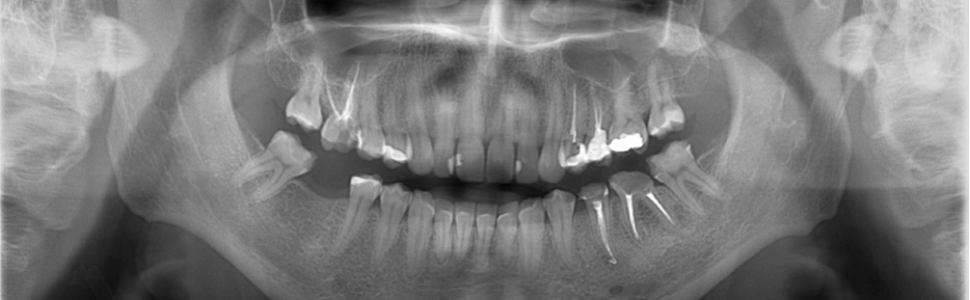

Celem pracy było opisanie ponownego leczenia endodontycznego zębów przedtrzonowych, które początkowo można błędnie ocenić jako zęby o nieskomplikowanej anatomii, teoretycznie łatwe do leczenia. Endodoncja to bardzo dynamicznie rozwijająca się dziedzina stomatologii, która umożliwia skuteczne wyleczenie zębów dawniej skazanych na ekstrakcję. W artykule przedstawiono różnorodność anatomiczną zębów przedtrzonowych na podstawie dwóch przypadków z własnej praktyki oraz wdrożone postępowanie diagnostyczno‑terapeutyczne. Długofalowe powodzenie leczenia kanałowego zależy nie tylko od wyjściowej diagnozy, stanu tkanek okołowierzchołkowych, ale także od prawidłowo przeprowadzonych procedur podczas leczenia. Dodatkowo warto zaznaczyć, że wyleczenie systemu kanałowego to dopiero początek drogi, a szczelna i trwała odbudowa zęba to również warunek konieczny do osiągnięcia sukcesu terapeutycznego oraz satysfakcji pacjenta.

The aim of this cases report was to present the endodontic treatment of premolars, which seemed to be easy and uncomplicated at the first sight. Endodontics is a very dynamically developing field of dentistry that enables effective treatment of teeth formerly qualified for extraction. The article presents the anatomical varieties of premolars based on two cases from own experience, introduced diagnostic and therapeutic procedures. The long‑term success of root canal treatment depends not only on the initial diagnosis, the state of periapical tissues, but also on correctly performed procedures during treatment. In addition, it is worth noting that CTR is just the initial step, and the proper restoration of the tooth is essential for a successful treatment and satisfied patient.